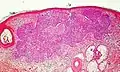

Other more specific subtypes of basal-cell carcinoma include:[19][2]

Type | Histopathology | Other characteristics | Image |

---|---|---|---|

Cystic basal-cell carcinoma | Morphologically characterized by dome-shaped, blue-gray cystic nodules.[2] | ![]() | |

Morpheaform basal-cell carcinoma (also known as "cicatricial basal-cell carcinoma", and "morphoeic basal-cell carcinoma") | Narrow strands and nests of basaloid cells, surrounded by dense sclerotic stroma.[20] | Aggressive[19]: 748 [2] | ![]() |

Infiltrative basal-cell carcinoma | Deep infiltration.[2] | Aggressive[2] | |

Micronodular basal-cell carcinoma | Small and closely spaced nests. | ![]() | |

Superficial basal-cell carcinoma (also known as "superficial multicentric basal-cell carcinoma") | Occurs most commonly on the trunk and appears as an erythematous patch.[19]: 748 [2] | ![]() | |

Pigmented basal-cell carcinoma exhibits increased melanization.[19]: 748 [2]: 647 | About 80% of all basal-cell carcinoma in Chinese are pigmented while this subtype is uncommon in white people. | ||

Rodent ulcer (also known as a "Jacob's ulcer") | Nodular, with central necrosis.[19]: 748 [2] | Generally a large skin lesion with central necrosis.[19]: 748 [2] | |

Fibroepithelioma of Pinkus | Anastomosing epithelial strands in a fenestrated pattern[21] | Most commonly occurs on the lower back.[19]: 748 [2] | ![]() |

Polypoid basal-cell carcinoma | Exophytic nodules (polyp-like structures) | Generally on head and neck.[2] | |

Pore-like basal-cell carcinoma | Resembles an enlarged pore or stellate pit.[2] | ||

Aberrant basal-cell carcinoma | Absence of any apparent carcinogenic factor, and occurring in odd sites such as the scrotum, vulva, perineum, nipple, and axilla.[2] |